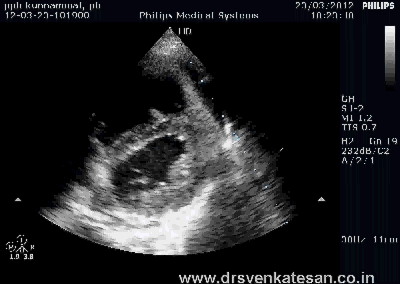

RV has some unique properties in terms of shape , size and hemodynamics . We are getting more insights from modern blood pool imaging by MRI , about how the RV handles the blood volume .

We know RV has a unique shape triangular ( partially pyramidal ) . It can be inferred the RV cavity is formed by fusion of many eccentric spacial planes. We have always believed RV handles the blood it receives from right atrium in a unique way .Now we are beginning to understand it .It is now documented the RV segregates the blood it receives into 4 components.